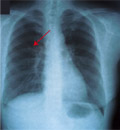

今回は「肺癌」のお話をします。図1、2は咳が続いていた40歳代の女性で、左肺に指先程度の小さなしこりがありました。入院して精密検査を受けましたが、しこりも小さく診断がつきませんでした。肺癌の可能性が考えられましたので手術を受けた結果、やはり肺癌でした。早期の肺癌で、手術により治癒しております。